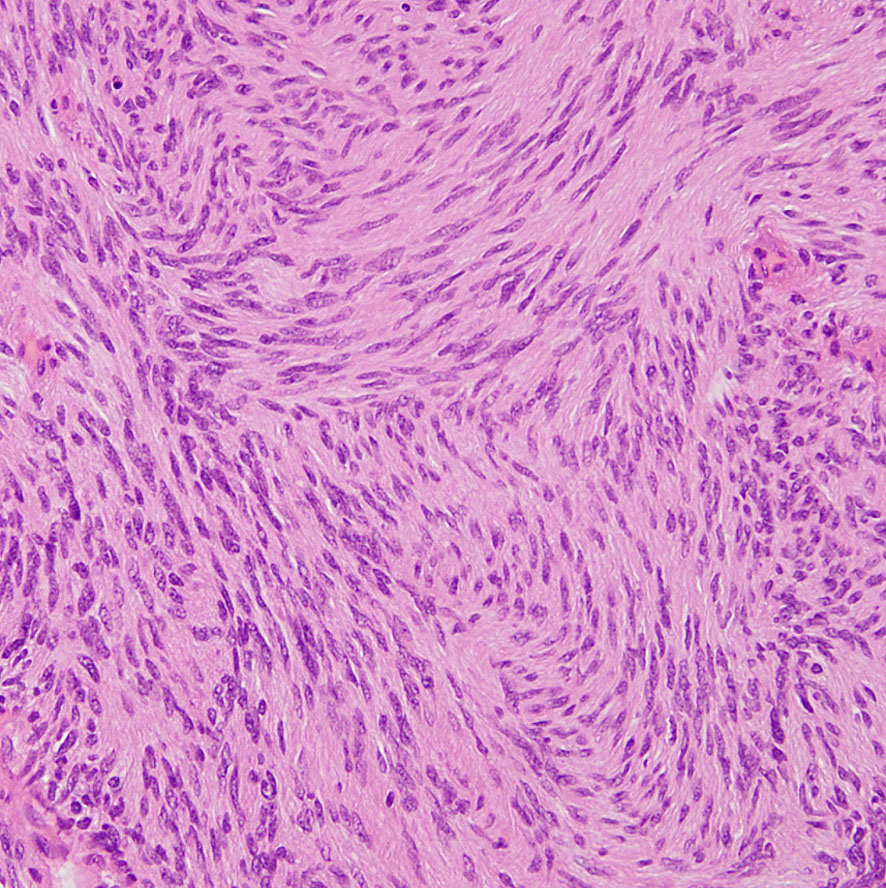

紡錐型の核を有する腫瘍細胞で構成されます。左側の写真のように,古典的病理所見として,束状 fascicular に配列する密な組織である Antoni A Typeと網状 reticular で疎な組織である Antoni B Typeが混在するパターンを示します。神経鞘腫では多少の核の異型性がみられても悪性像とはいえません。嚢胞を形成したり,時には毛細血管拡張 simple hemangioma を思わせるような著明な血管の増生があり腫瘍内出血をきたすことがあります。

隣り合う細胞核の柵状配列 nuclear palisade arrangement (palisading) は,髄膜腫との鑑別での大切な所見です。